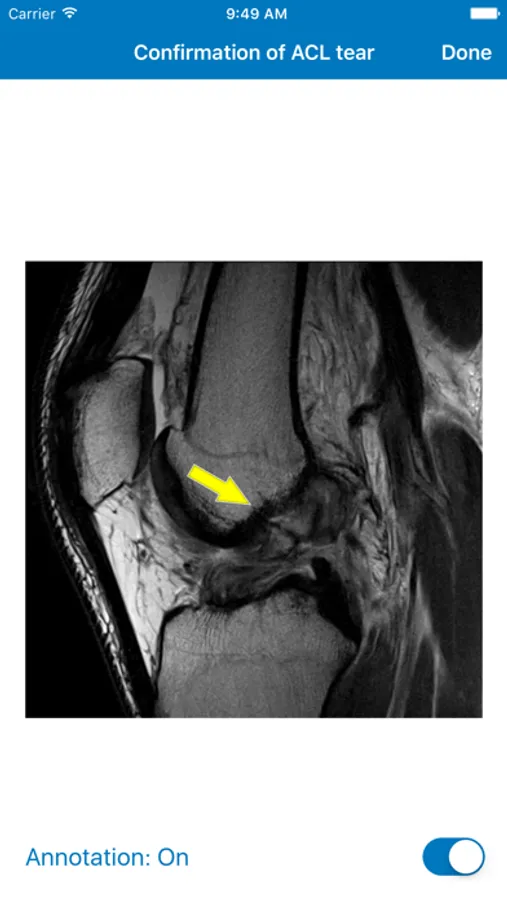

The Sideline Guidelines App is an educational tool intended for medical providers on the sidelines treating athletic injuries for high school, college, and professional athletes. A national faculty has compiled a summary of expert knowledge to help diagnose athletic injuries (history, physical examination, and imaging), determine the ability of athletes to play their sport, recommend treatment in the training room and beyond, and estimate return to play time. This information is presented in a highly structured and searchable format that allows quick access to key points to consider when making an informed medical decision.